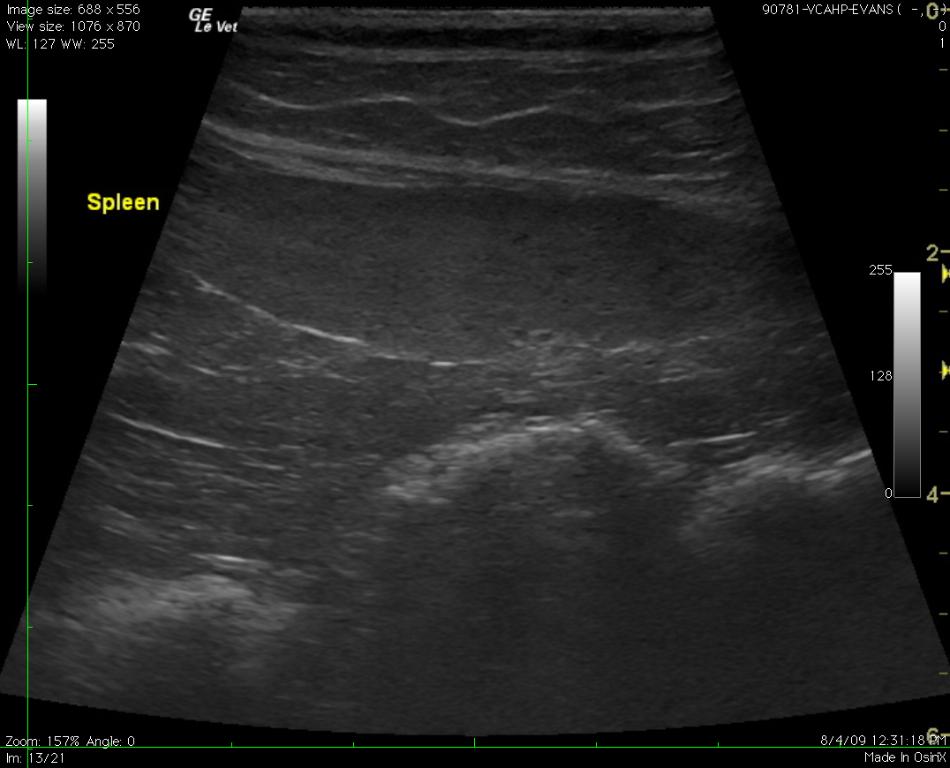

A 10-year-old MN DLH presented for vomiting, depression, and weakness. Clinical exam findings were uneventful. The complete blood count revealed anemia (PCV 16% – 3+ anisocytosis, 2+ polychromasia, 2+ rouleaux present), neutropenia 1659 (n 2500-8500) and lymphocytopenia 273 (n 1200-8000). Blood chemistry revealed slightly elevated total bilirubin.

A 10-year-old MN DLH presented for vomiting, depression, and weakness. Clinical exam findings were uneventful. The complete blood count revealed anemia (PCV 16% – 3+ anisocytosis, 2+ polychromasia, 2+ rouleaux present), neutropenia 1659 (n 2500-8500) and lymphocytopenia 273 (n 1200-8000). Blood chemistry revealed slightly elevated total bilirubin.